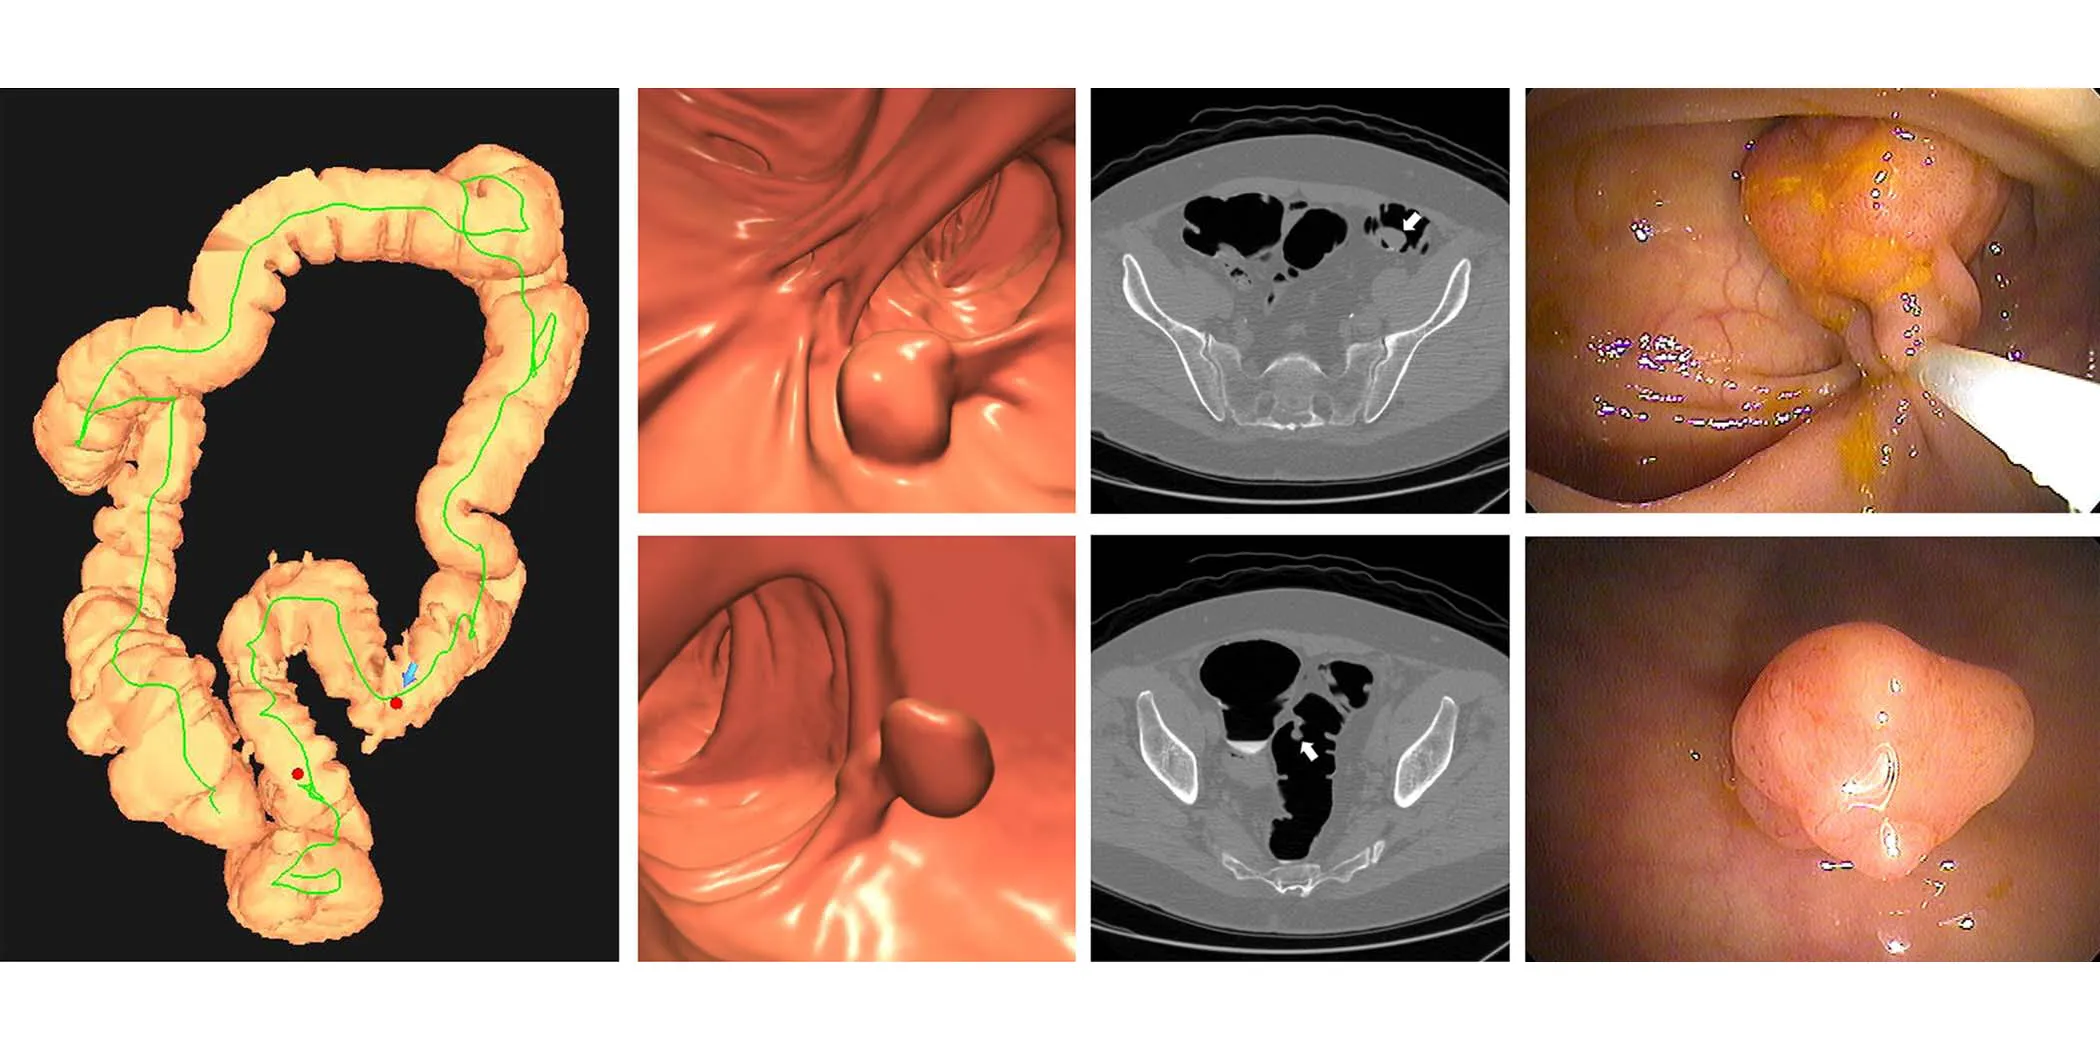

Multitarget stool DNA (mt-sDNA), which analyzes stool samples for specific colorectal cancer biomarkers, and CT colonography, which uses CT scans to examine the colon and rectum for cancer or polyps, are both now covered procedures for Medicare recipients.

According to Pickhardt, both stool DNA testing and CT colonography are less invasive and much safer primary screening options. However, with two inherently different screening methods, Pickhardt and colleagues set out to analyze mt-sDNA and CT colonography in a head-to-head comparison of clinical efficacy and cost-effectiveness.